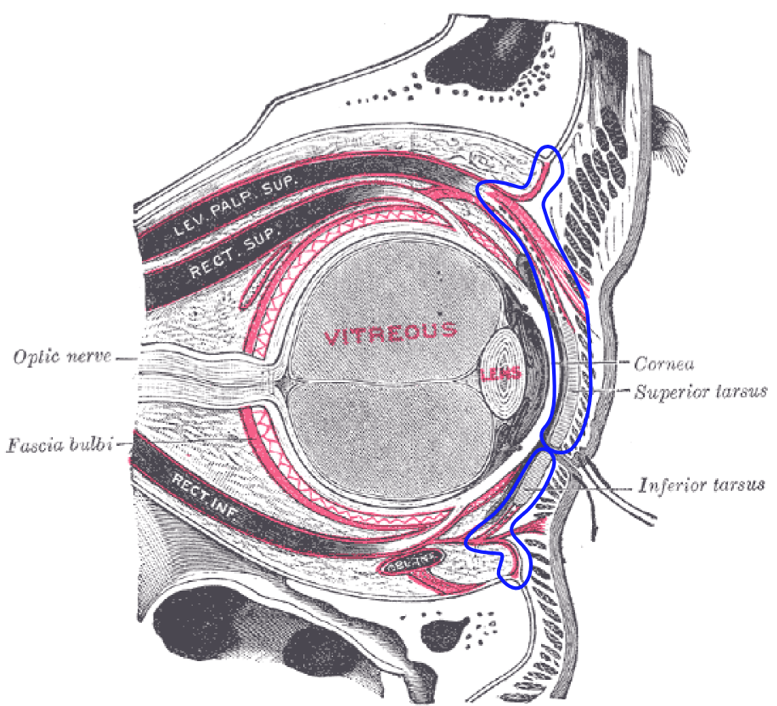

Periorbital Cellulitis

- Periorbital cellulitis is the infection that is anterior to the septum of the eye.

- Primary causes are trauma or nearby infection such as sinusitis.

- Needs to be differentiated from orbital cellulitis.

- On ocular ultrasound, you will see the thickening of the palpebral tissue.

- If severe, you may also see signs of abscess.

- Figure 9. The blue line denotes the ocular septum (courtesy of Mikael Häggström, 20149)